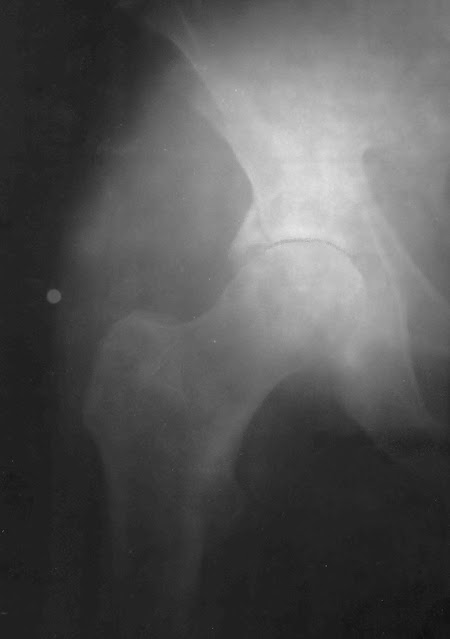

В первые годы после синостоза ГБК и ШБК на границе

между ними рентгенологически обнаруживается полоска плотного костного вещества

– эпифизарный шов, который иногда сохраняется и у стариков (Дьяченко В.А.,

1954). Наличие эпифизарного шва позволяет судить о величине угла Альсберга в

период завершения синостозирования, а, следовательно, и уточнить особенности

развития бедренной кости. Угол наклона линии эпифизарного шва к горизонтали

составляет порядка 16° (Рис.3.28) (Huggler A.H., 1968).